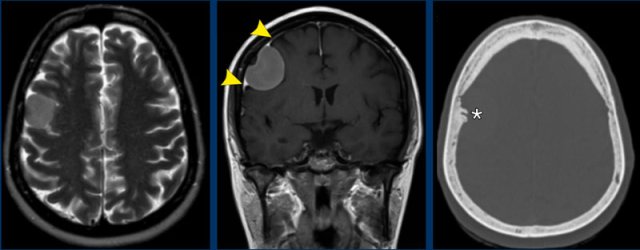

Lymphoma

This

patient had multiple osseous FDG-PET positive lesions.

A

biopsy of a tibial lesion demonstrated a malignant lymphoma.

He also presented with a dural based mass with additional subtle leptomeningeal involvement.

The lesion demonstrates homogeneous enhancement and restricted diffusion.

Primary dural lymphoma is an extranodal non-Hodgkin

lymphoma that accounts for less than 1% of all central nervous system

lymphomas.

It can mimic the appearance of a meningioma and

meningiomas can sometimes show restricted diffusion, especially when it is an atypical or malignant meningioma.

In this patient, a multifocal dural lymphoma was diagnosed.

Images

Multiple enhancing extra-axial located dural based lesions with restricted diffusion.